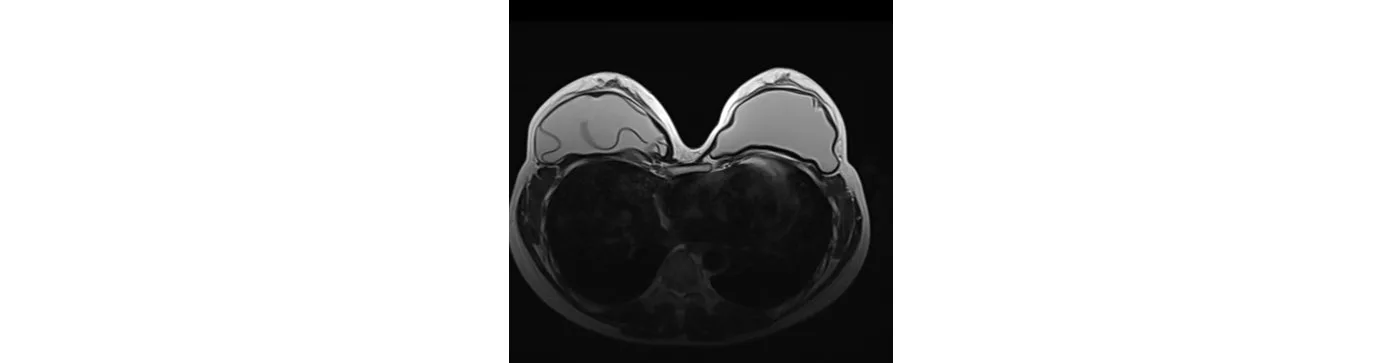

A 36-year-old female has a check-up after 5 years of breast augmentation. The MRI diagnosed implant rupture in the right chest.